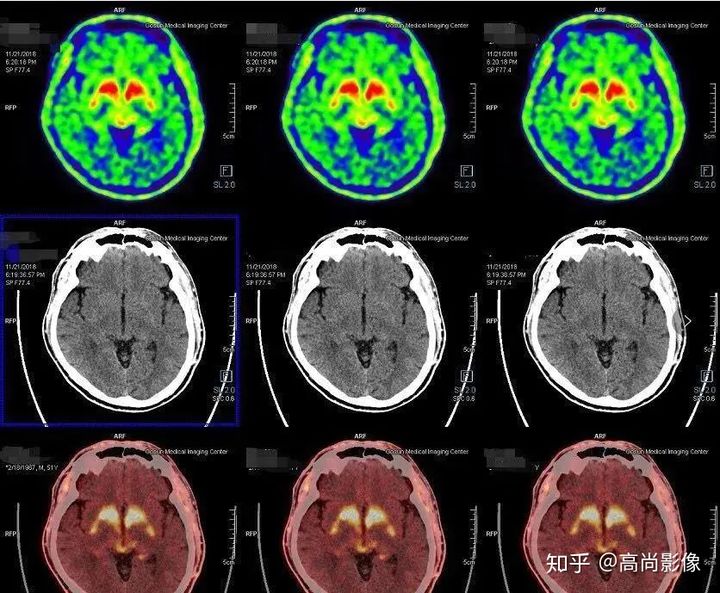

發(fā)作間期癲癇灶呈代謝減低

發(fā)作期癲癇灶呈代謝增高